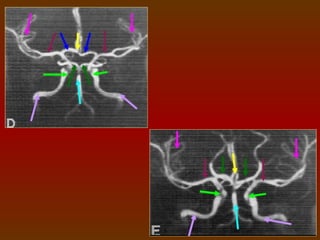

CÍRCULO OU POLÍGONO DE WILLIS

É um círculo de artérias que suprem o cérebro. Foi nomeado em

homenagem a Thomas Willis (1621 – 1873), médico inglês.

A. Cerebral

A. Comunicante

Anterior Direita

Anterior

A. Carótida

Interna Direita                               A. Cerebral Anterior

Esquerda

Média                                     A. Carótida Interna

Posterior Direita                               A. Comunicante

Posterior Esquerda

Posterior Direita                                 A. Cerebral

A. Basilar

CIRCULAÇÃO SANGUÍNEA DO CÉREBRO

O sangue chega ao cérebro através das artérias vertebrais e

das artérias carótidas internas, que se comunicam através do

polígono de Willis, este é uma anastomose arterial que fornece o

suprimento sangüíneo para os hemisférios cerebrais, sendo

formado pelas artérias cerebrais anteriores e posteriores, artérias

comunicantes anterior e posteriores e pela carótida interna.

COMPONENTES

 Artéria cerebral anterior (direita e esquerda).

 Artéria comunicante anterior.

 Artéria carótida interna (direita e esquerda).

 Artéria cerebral posterior (direita e esquerda).

 Artéria comunicante posterior (direita e esquerda).

IMPORTÂNCIA FISIOLÓGICA

O arranjo das artérias no

Polígono   de    Willis    cria uma

redundância na circulação cerebral.

Se uma parte do círculo estiver

bloqueada ou estreitada (estenose),

ou se uma das artérias que suprem o

polígono    está     estreitada  ou

bloqueada, o fluxo sanguíneo dos

outros vasos sanguíneos podem

muitas vezes preservar a perfusão

cerebral .

ESTUDO DO POLÍGONO DE WILLIS

 1 mm espessa X 1 mm incremento.

 Em média 100 ml de contraste, a 3ml/s.

A marcação vai da

base do seio

esfenoidal ao topo

do corpo caloso.